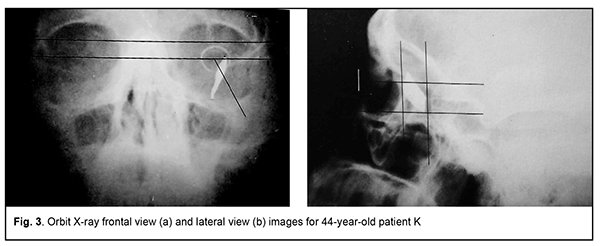

Introduction Ocular trauma is still a leading cause of loss of vision and legal blindness and vision impairment. Intraocular foreign bodies (IOFBs; such as metal, glass, rock, etc.) are seen in 15%-40% of penetrating ocular injuries [1, 2]. IOFBs sized 1-2 mm are most common and can cause early and late complications (endophthalmitis, metallosis, etc.) which are more significant in terms of their effect on health than the trauma caused by such a body itself. IOFBs sized more than 5 mm commonly cause significant damage to the eye, and may lead to loss of not only vision, but also of the whole eye. Accurate IOFB localization is essential for the success of IOFB removal. Until recently, orbit X-ray in two views using the Comberg-Baltin prosthesis was the primary imaging modality for localizing radiopaque IOFBs. Although other modalities can be used today for localizing radiopaque IOFBs, they do have certain diagnostic disadvantages. Because the X-ray method of foreign body localization is widely available, cost-effective, and offers sufficient accuracy for surgical planning, it is still relevant. It is used in combination with contemporary imaging modalities (CT, ultrasound, etc.) and, if these are unavailable, it can be used as the primary imaging modality. Although the ultrasound method is, undoubtedly, of value in localizing IOFBs, especially radiopaque ones, it cannot localize the IOFB accurately enough to remove the latter immediately. In addition, it is effective only if combined with the X-ray method. Computed tomography (CT) scan provides more differentiated images of ocular tissue and media, and can identify IOFB and precisely locate it with respect to the adjacent ocular structures in most cases. CT is the indispensable imaging examination technique in the presence of numerous IOFBs, but is not always effective in determining IOFB size and shape. In CT scans, a foreign body sized less than 3 mm appears as a regular round body, and that sized 3 to 7 mm appears as an irregularly round or oval-shaped body, although the actual size and shape may differ from those seen in the CT. CT images of metal IOFBs often suffer from bright and dark streak artifacts that radiate from the shadow of metal IOFB. If there is any possibility that the foreign body may be metallic, magnetic resonance imaging (MRI) should not be performed because of possible movement of the object and consequent damage to intraocular structures. Scleral subconjunctival hemorrhage is more commonly caused by larger IOFBs. In addition, hypertrophy of the scleral conjunctiva surrounding the limbus may arise from other causes such as allergic response, burns, consequences of severe concussion, etc. Marking the position at the limbus presents some difficulties in the presence of apparent chemosis or scleral subconjunctival hemorrhage. As it is difficult or impossible to make the Baltin prosthesis adjacent to the limbus under these circumstances, other methods have been proposed for marking the position at the limbus. Baltin [3] proposed to apply bismuth pulp to mark the limbus at 6 and 12 o’clock axes with a (preferably plastic) probe when the lids are separated with eye speculum. Bismuth pulp spreads over the eye and is washed away by tears rather frequently. In addition, the eye must be kept immobile during examination, which is almost impossible. Vodovozov [4] proposed to mix bismuth or barium sulfate with nitro-glue or collodion, make small silver-paper half-discs and soak them in this mixture, and use them to mark the limbus. These adhere well to the limbus, are not washed away by tears, and exhibit no displacement during movements of the eye. Poliak [5-6] proposed to introduce T-shaped studs beneath the conjunctiva at the limbus at 3 and 9 o’clock axes. Adhering, suturing or fastening various radiopaque markers at the limbus causes incongruous shadows on X-ray films, and can result in increased damage to the eye. Because radiopaque objects are placed by sight and hands and in one plane, approximately at certain meridians, location of the IOFB in the eye is estimated with a significant error. Marking the center of the cornea with a probe, dressing forceps, or other methods (Plittas, 1941; Bogatin, 1949; Madroszkiewiz, 1954, etc) have not been widely implemented due to their small effect [7]. A limbal ring (internal diameter, 12 mm) made of 1-mm thick wire, which is sutured or adhered to the conjunctival sclera, cannot mark the limbus in cases of hypertrophy of the scleral conjunctiva, and it is difficult or impossible to make the ring adjacent to the limbus. In addition, it should not be used in the presence of fresh, gaping wound [8-10]. Gardona and Trokel [11] used a soft vacuum lens for X-ray localization of foreign bodies in eyes with maintained corneal sphericity. Such a lens remains well secured and does not change its position over the cornea, which facilitates adequate localization of the IOFB. Taking into account the relevance of the problem, we have been looking for a new way to solve it. We made a corneal prosthesis (limbus marker; Innovation Proposal No. 556/54 dated 12.07.1989), which is a rigid corneal contact lens (optical power, 0D; diameter, 11 mm; thickness, 0.3-0.35) made of polymethylmethacrylate. The lens has 0.5-mm lead marks in four quadrants (3, 6, 9 and 12 o’clock); lead mark edges and lens edges coincide with each other. The distance between external contours of adjacent marks is 11 mm, and the distance between internal contours is 10 mm. The prosthesis is well fit in the specified position over the cornea during X-ray examination. It can be used if the conjunctiva and lens are abnormally spherical in shape (chemosis and/or subconjunctival hemorrhage) and in the presence of a fresh scleral wound. The purpose of the study was to improve the accuracy of X-ray localization of foreign bodies in the presence of apparent chemosis or scleral subconjunctival hemorrhage through the use of the ring-shaped limbus marker. Material and Methods We proposed a method for marking the limbus during X-ray localization of foreign bodies in the presence of apparent chemosis or scleral subconjunctival hemorrhage through the use of the ring-shaped limbus marker (Patent of Ukraine No. 12,015 issued 25.10.2017; Bulletin No. 20). The ring is made from 0.5-0.7-mm stainless steel wire. Rings with external diameters of 10, 11 and 12 mm were made for examining eyes of different sizes. The examination procedure was as follows. After epibulbar anesthesia, a sterile ring-shaped limbus marker of the appropriate size was placed on the cornea against the limbus. It was well fit in the specified position due to hypertrophy of the conjunctiva surrounding the cornea, and corresponded to the conjunctival attachment to the limbus. The posterior-to-anterior (frontal view) orbit X-ray was taken as per the technique described by Itsykson (using the grating), which allowed for control of the eye and limbus marker for correct position during roentgenography. In lateral or axial view, the shadow of ring-shaped limbus marker appeared as a straight line, and in a PA view, it appeared as a ring. Orbit X-ray was performed, quality of X-ray films was assessed and IOFB position in the eye was calculated using the technique of Comberg-Baltin or Abalikhin-Pivovarov. In order to determine the projection of the anteroposterior axis of the eye, the measurement scheme was put on the PA X-ray film so to get the limbus marker shadow inside the relevant circle of the scheme. Thereafter, the needle was used to puncture the PA X-ray film through the measurement scheme and at the intersection of horizontal and vertical meridians. This puncture point at the X-ray film corresponded to the projection of the antero-posterior axis of the eye. Ring-shaped limbus markers with external diameters of 11 and 12 mm were utilized in 10 cases and 2 cases, respectively, in the presence of limbal conjunctival hypertrophy. Results In 12 patients, IOFB was successfully removed based on the data obtained from X-ray localization by means of the ring-shaped limbus marker. In two patients without limbal conjunctival hypertrophy, foreign body X-ray (PA view and lateral view) localization was performed by means of the Baltin’s prosthesis. Thereafter, these two received a paralimbal subconjunctival injection of 0.9% NaCl, and foreign body X-ray localization was performed by means of the ring-shaped limbus marker. Calculations for X-ray (PA view) localization by means of the Baltin’s prosthesis were in agreement with those for X-ray (PA view) localization by means of the ring-shaped limbus marker. In addition, with regard to the X-ray lateral view and X-ray axial view, the position of the IOFB relative to the ring-shaped limbus marker was 1 mm deeper than that relative to the Baltin’s prosthesis due to the location of the limbal circle in the eye. Figs 2 and 3 present X-ray films (frontal projection, a; and lateral projection, b) of the orbit and ring-shaped limbus marker taken on two patients. Example Case 1 A 43-year-old man sustained injuries from a battery explosion. At admission to the trauma centre, he was diagnosed with Poliak grade 1-2 chemical (battery acid) burn to face, conjunctiva and cornea, and a suspected foreign body in the left eye. OD: His right eye was normal. OS: His uncorrected visual acuity in the left eye was 0.1. There was photophobia and subconjunctival hemorrhage, and the bulbar conjunctivae showed a marked collar of edema at the limbus. A 2-3-mm conjunctival wound was found 5 mm from the limbus at the 8 o’clock meridian. The left eye showed subtotal corneal erosion and edema. The left anterior chamber was of moderate depth. The pupil was round and reactive to light. A pink fundus reflex was observed. Fundus structures were poorly seen. The intraocular pressure (IOP) was normal. A shadow of metal IOFB measuring 1х1х2 mm was seen in X-ray films (frontal projection and lateral projection) of the orbit and limbal circle. In the frontal view of orbital X-ray with the ring-shaped limbus marker, the IOFB was seen along the 8:40 o’clock meridian, 9-11 cm from the sagittal axis of the eye, and 1.5-3 mm beneath the horizontal meridian of the eye. In the lateral view of orbital X-ray with the ring-shaped limbus marker, the IOFB was seen 1.5-4 mm posterior to the conjunctival attachment to the limbus, and 1.5-3 mm beneath the horizontal meridian of the eye. The sagittal axis of the eye was 24 mm long. That is, the IOFB was along the 8:40 o’clock meridian, 1.5-4 mm posterior to the conjunctival attachment to the limbus, and 9-11 mm from the sagittal axis of the eye, i.e., within the scleral subconjunctival hemorrhage region. Example Case 2 A 44-year-old man sustained a left-eye injury due to a power lawnmower. At admission, he was diagnosed with the penetrating sclera wound, vitreous hemorrhage and IOFB in the left eye. OD: His right eye was normal. OS: Visual acuity was light perception with inaccurate projection of rays OS. The corneal and sclera wound was linear and vertical, 9-10 mm in length at 2 mm from the limbus at the 3 o’clock meridian; it was seen between 4-5 mm above and 4-5 mm beneath the horizontal meridian. There was scleral subconjunctival hemorrhage around the limbus. The anterior chamber was filled with blood. The IOP estimated by palpation was significantly decreased. In the frontal view and lateral view of orbital X-ray with the ring-shaped limbus marker, the shadow of IOFB measuring 4х7.5х21 mm was seen in the inferior lateral quadrant of the orbit, 3-20 mm from the sagittal axis of the eye, and 20-30 mm posterior to the conjunctival attachment to the limbus, i.e., within the posterior pole wound. In addition, a 2-3-mm portion of the IOFB was situated in the vitreous, and the rest portion extended beyond the eye to the orbit.